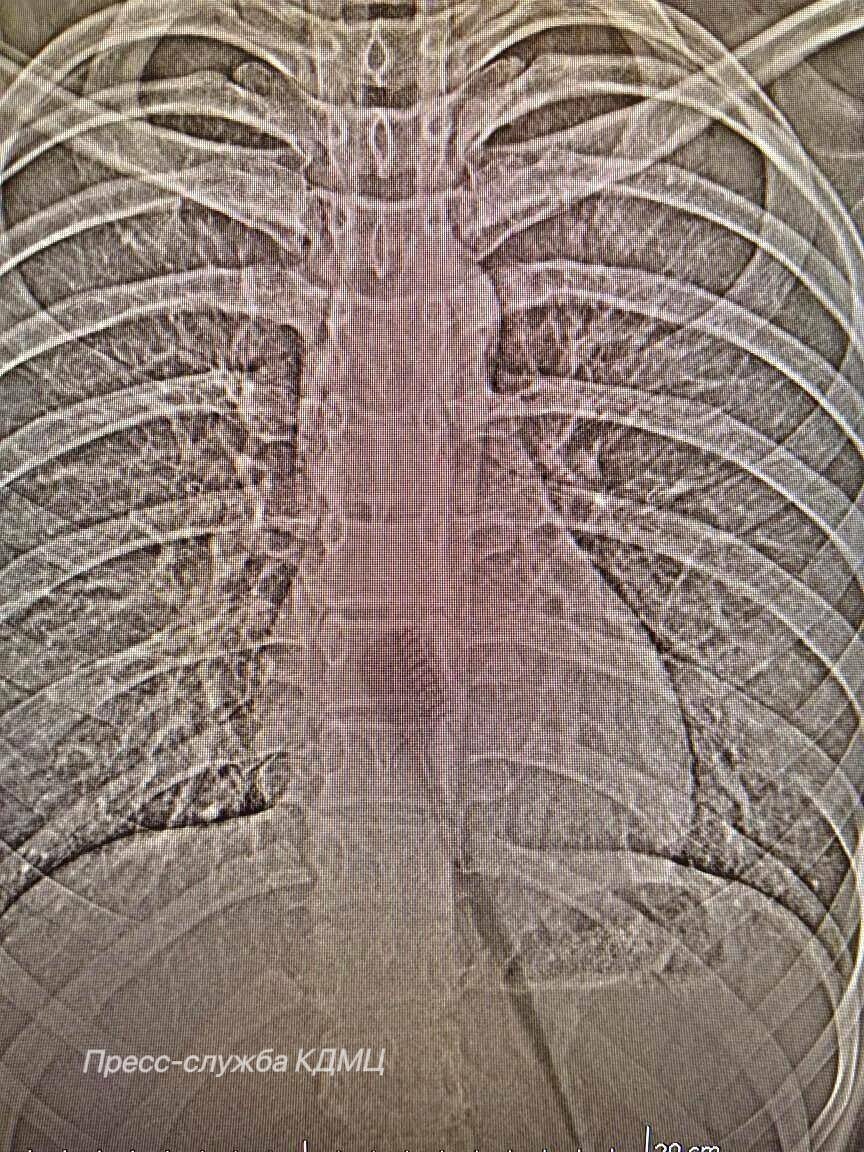

13-летняя девочка случайно проглотила её во время чистки зубов - по словам врача, это мог спровоцировать резкий вдох или непроизвольное сокращение мышц глотки.

Щётка частично находилась в пищеводе и представляла риск повреждений. Предмет удалили эндоскопически, что позволило избежать осложнений и ускорить восстановление пациентки.